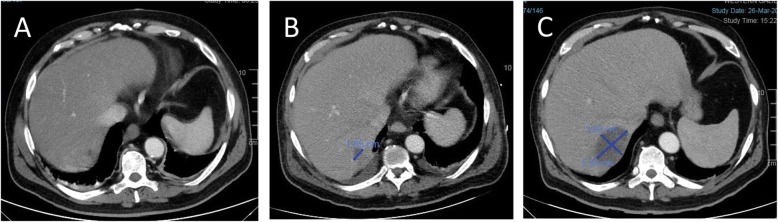

Two weeks after discharge the patient underwent an EUS, which demonstrated a gallbladder with gallstones and sludge. Biliary duct dilation of up to 6.4 mm with 2 filling defects were also visualized. An ERCP was recommended and performed a week and a half later. A papillotomy and stone fragment extraction using a balloon catheter and a basket were performed. After the ERCP, the patient was admitted to our department for observation. Twenty-four hours post-ERCP the patient developed a fever (38 °C), chills, hyperbilirubinemia (2.66/1.16 mg/dl) and elevated liver function tests (AST 224 U/L, ALT 121 U/L, ALP 160 U/L, GGT 570 U/L). Ascending cholangitis was empirically treated using Ceftriaxone and Metronidazole. However, he continued to be febrile, confused and with chills. His physical examination was remarkable, his abdomen was diffusely tender and his lab tests reveal an increasing in inflammatory markers: C-reactive protein (CRP) 256 mg/l, leukocytosis 14(× 10 [ref. 3]/ul),with left shift 92% neutrophils. Also markedly hyperbilirubinemia was observed (total bilirubin 5.53 mg/dl), Blood cultures were drawn to rule out a viscous perforation. A computed tomography (CT) scan with double contrast of the abdomen and pelvis was done 3 days post-ERCP. A perforation was ruled out as no abdominal free air or fluids were found. Yet a very small hypodense lesion was found in the seventh liver segment (Fig. 1a).

On day 6 post-ERCP, the antibiotic regimen was changed to Ertapenem and Vancomycin, to treat possible multi-drug resistant pathogens. Two days later, extended-spectrum beta-lactamase positive Klebsiella Pneumonia and Enterococcus Hirae were identified on blood cultures so antibiotics were switched to Imipenem and Cilastatin. Nonetheless, the patient continued to have abdominal pain. Upon examination, his abdomen was soft and distended, with no signs of peritonitis. CRP was elevated (160 mg/L), with mild leukocytosis (13 x 10e3/uL) and neutrophilia (83%). CT scan, with a double contrast of the abdomen and pelvis was repeated on day 7 post-ERCP revealing a hypodense irregular lesion that was found to increase in diameter, this finding was consistent with pyogenic liver abscess (Fig. 1b). Also, a hypodense lesion in the right psoas appeared (Fig. 2b), which was not seen on the first CT scan (Fig. 2a), it was decided to continue with antibiotic treatment without drainage. Two days after the antibiotic regimen was changed to Imipenem and Cilastatin, the abdominal pain subsided. He was afebrile and his liver function tests and bilirubin normalized. However, on day 10 post-ERCP, the patient began to complain about low back pain and difficulty walking. On physical examination, he had localized tenderness over the spinous processes of L4-L5, and reduced quadriceps femoris strength (3/5). A thoracolumbar spine magnetic resonance imaging (MRI) scan was recommended by a consulting orthopedic surgeon to evaluate for possible myelopathy or radiculopathy. MRI was performed on day 19 post ERCP, which revealed L4-L5 discitis,a large iliopsoas abscess on the right side,and other small abscess on the left side, an epidural abscess in front of spinal canal at level L1-D11 other one at level L2- S1 appearing to compress the spinal cord (Fig. 3). A diagnosis of spinal epidural abscess (SEA) with discitis and osteomyelitis was established. The patient was transferred to the orthopedic department and was urgently operated. Decompressive laminectomy of L5 was done and a large epidural abscess was drained and irrigated. Drainage catheters were placed, and the wound was closed in layers. Cultures from the pus were positive for Klebsiella pneumonia. Thus, IV antibiotics with polymyxin E and Gentamicin were initiated Post-operatively, and the patient’s back pain significantly subsided. Nonetheless, due to continued of serosanguineous drainage from the surgical incision, fever of 38.7C, CT total body was performed on day 7 postoperative to evaluate epidural and liver abscess, exhibited a 4.8 cm hypodense irregular lesion at segment 7 of the liver,epidural and psoas abscess were increased in size (Figs. 1c,2c). patient was taken back to the operating room for other evaluation. The decompressive laminectomy was expanded to include L2-L4, and multiple irrigations were done. Gentamycin and Vancomycin containing polymethylmethacrylate beads were implanted locally and drainage catheters were placed before wound closure. The patient was continued intravenous antibiotics with polymyxin E and Gentamicin. Two days later the patient was presented to the multidisciplinary panel (surgery and radiology) for further evaluation and discussion of liver and iliopsoas abscess treatment options. In light of the clinician and laboratory improvement it was decided to continue with a non invasive approach and to complete 6 weeks of antibiotic treatment. During the subsequent days the patient’s condition improved, the surgical incision was inspected without signs of infection or leak, and his lap tests normalized. Two months later,abdominal and spinal cord CT scan was performed as part of the follow up examination which assured almost complete regression of liver and iliopsoas abscess. An interval cholecystectomy was performed 6 weeks after discharging.